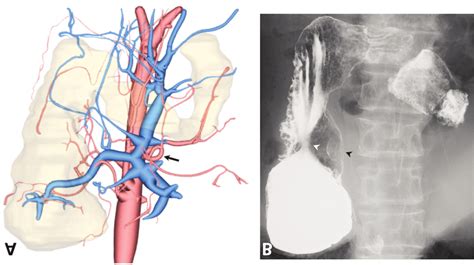

- Preoperative 3-dimensional Reconstruction Of A Computed Tomography ...